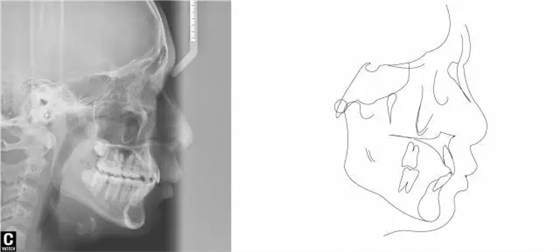

術(shù)后全景,側(cè)位照。

640.webp (28).jpg

幾何畫板技術(shù)完成術(shù)后頭影測(cè)量!

640.webp (29).jpg